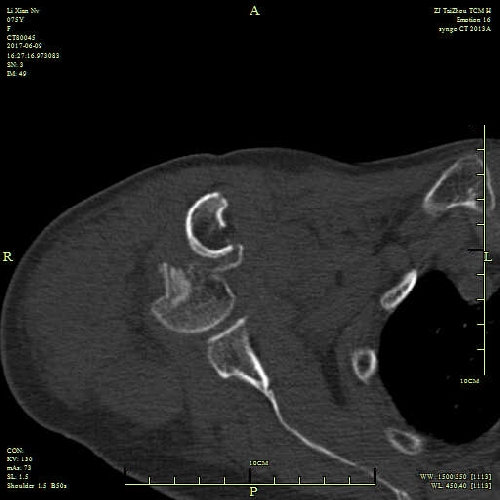

近日,我院骨三科獨(dú)立完成了首例 “人工肱骨頭置換術(shù)”?;颊呃頧X,女,75歲,因摔傷致右肩腫痛、活動(dòng)不利4小時(shí)入院。查體判斷:右肩部無(wú)腫脹,局部壓痛,縱向叩擊痛陽(yáng)性,右肩上舉、外展受限,肢端血循、感覺(jué)良好。X片示:右肱骨近端粉碎性骨折,移位明顯。CT示:右肱骨上端骨質(zhì)斷裂,呈粉碎性,大、小結(jié)節(jié)骨折,斷端位置差,關(guān)節(jié)在位。診斷為:右肱骨近端粉碎性骨折(四部分骨折)。為了緩解患者疼痛,改善肩關(guān)節(jié)功能,提高生活自理能力,經(jīng)科室討論決定,對(duì)于高齡肱骨近端粉碎性四部分骨折,應(yīng)采用人工肱骨頭置換術(shù)。

術(shù)前CT 術(shù)前CT